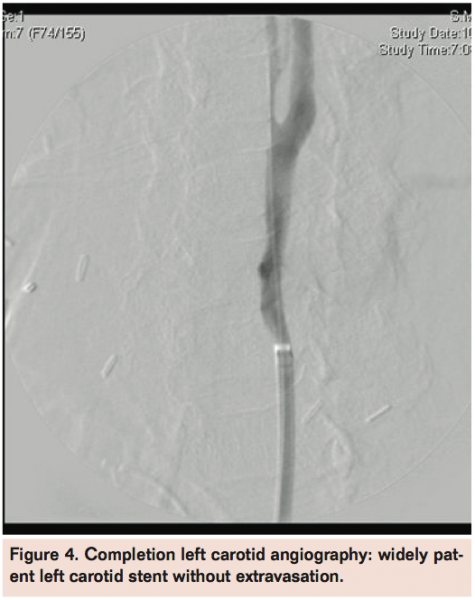

For the male patient, extravasation was visualized at the left common carotid artery at the thoracic inlet (Figure 1). For the female patient, carotid fistula was visualized at the left common carotid artery in the low cervical area (Figure 2).

In both cases, an iCast covered stent (Atrium Medical) (no cerebral protection used) was deployed across the common carotid at the area of extravasation. The hemorrhage was controlled. Completion left carotid angiography was performed and revealed widely patent left carotid stent with free flow of contrast noted intracranially (Figures 3 and 4). Intracranial views confirmed free flow of contrast without evidence of large-vessel intracranial obstruction. The procedure was then completed and the wire and sheath removed, followed by deployment of a 6 Fr Angio-Seal device (St. Jude Medical) achieving hemostasis. The patient was then taken to the recovery room.